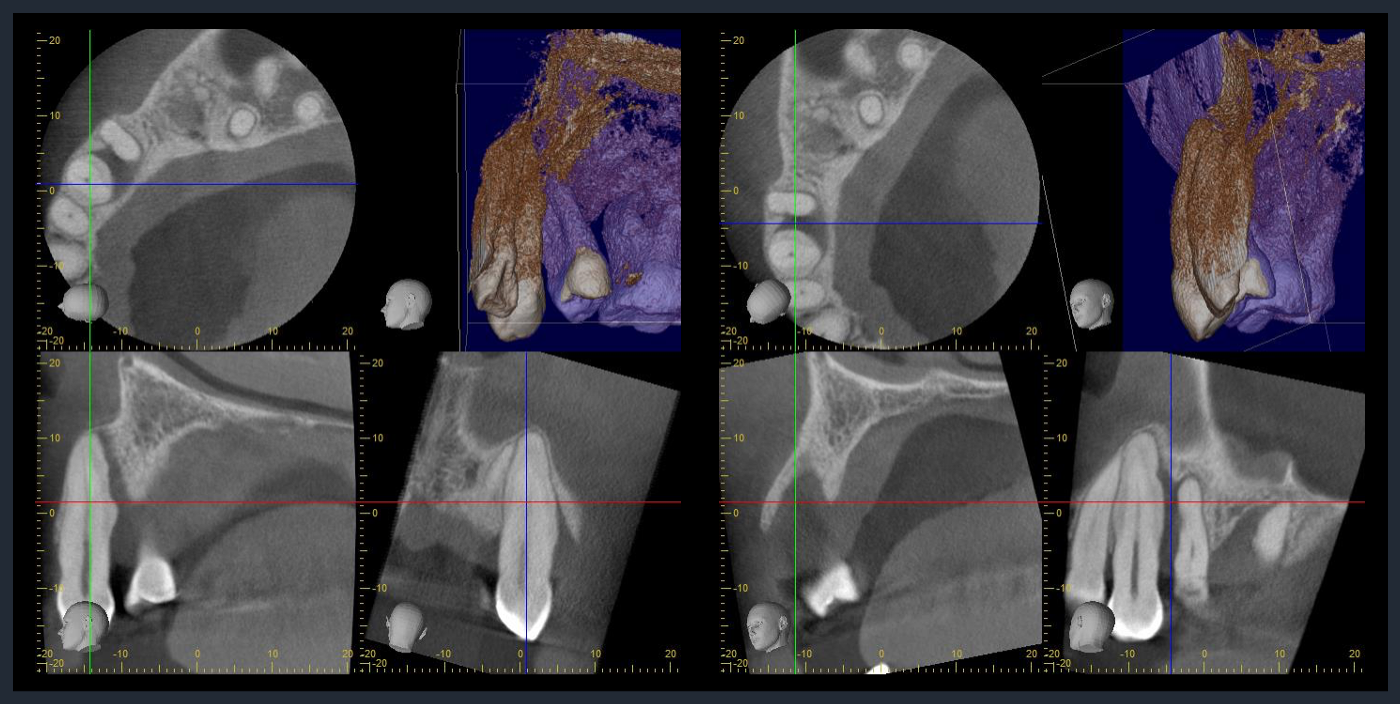

CTでの術前診査1

歯周基本治療後の再評価

Post-treatment evaluation

Post-treatment evaluation

CTでの術前診査2